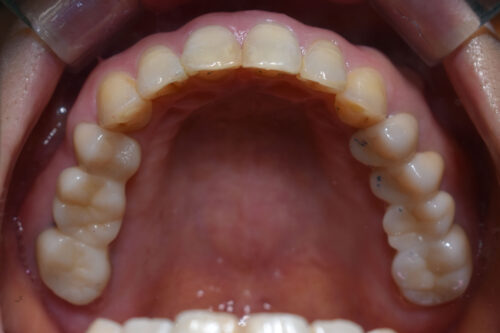

初診時年齢 46歳 女性

歯のでこぼこ(叢生)

左側完全クロスバイトの治療を

左側の小臼歯部から

大臼歯部にかけて

クロスバイトを呈し

過蓋咬合の状態でした。

ワイヤー矯正治療1年2か月後です。